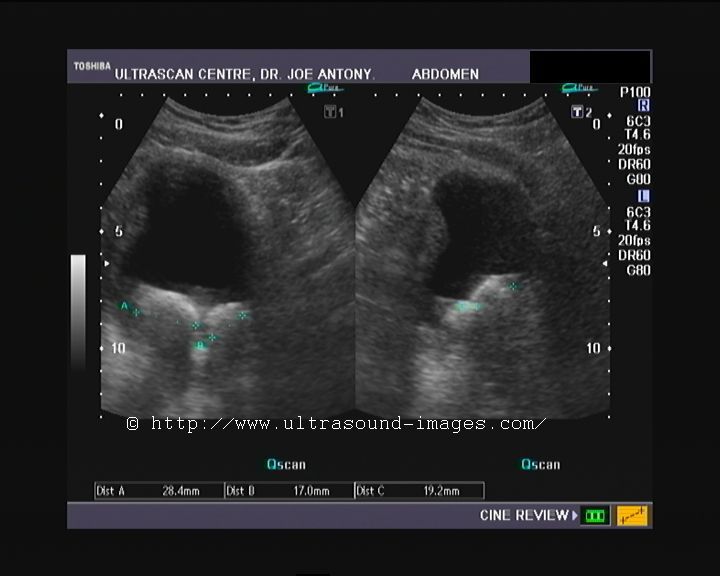

Urinary bladder wall trabeculation in a case of Lower urinary tract obstruction

Sonography of the urinary system was done on this elderly male patient having lower urinary tract symptoms. Ultrasound images show evidence of trabeculation of the urinary bladder. This is seen as folds of hypertrophied bladder mucosa and bladder smooth muscle. There is also evidence of bilateral moderate hydronephrosis (image top right). The cause of Lower urinary tract obstruction appears to the enlarged prostate (benign prostatic hypertrophy) with intravesical enlargement of the median lobe (image on lower left). The fourth image shows significant post-voiding residual urine in the urinary bladder (Ultrasound image on lower right).

Bladder trabeculation has been graded from 0 to 3 as:

grade 0- no trabeculation.

grade1- mild: area affected is less than 1/2 of the bladder and depth of trabeculation less than 5 mm.

grade2- moderate: area affected is greater than 1/2 of the bladder and depth of trabeculation is 5 to 10 mm.

grade 3- severe: area affected is greater than 1/2 of the bladder and depth of trabeculation is greater than 10 mm.

All images by Joe Antony, MD, using a Toshiba Nemio-XG ultrasound system.